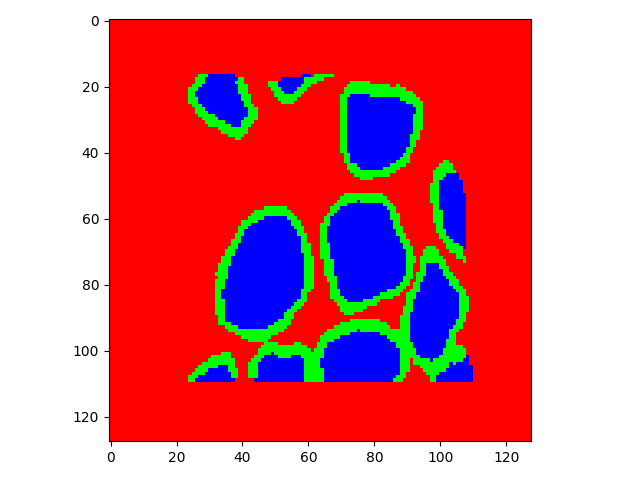

The task of nuclei segmentation can be roughly divided into two stages: the first stage is extracting the foreground(nuclei), the second stage is segmenting the connected foreground area into separated nuclei and finding out the boundary of each nucleus. Our method intends to merge these two steps by extracting the nuclei and their edges at the same time. That is the reason why it is named ”nuclei-boundary(NB) model”. As shown in Fig.3, the output of the NB model has three channels, each has the same height and width with the input image. Its values represent the probabilities of each pixel being , or class, respectively. The manual annotation for our segmentation problem is the boundary of each nucleus. A pixel belonging to the class means that it is on or inside an annotated boundary and within 2 pixel from the boundary. Pixels of the class are those that are inside annotated boundary but are not pixels. Correspondingly, the output can be regarded as an RGB image and the estimated maps of the , and are represented by red, green and blue, respectively, as shown in Fig.3. To generate the ternary mask for training, we apply a morphology operator to each nucleus to obtain the pixels, and then subtract pixels from the nucleus to get pixels.

Figure 6 shows how our method segments the nuclei step by step. The color variety is well controlled by the color normalization procedure. The prediction result shows clear nuclear areas and nucleus boundaries. In the final segmentation result and ground truth image, each nucleus is represented by a different color.